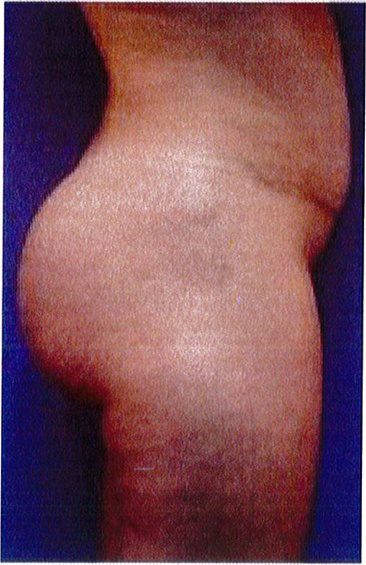

Hình. 19. . (A) Hình anh trước và (B) và sau phẫu thuật làm đầy mông của bệnh nhân chùng da vùng mông tương đối nhiều. Bệnh nhân được đặt khối implant dưới cân thể tích 330 mL ở hai bên.

Bệnh nhân 52 tuổi xuất hiện chùng da vùng mông (mức độ nặng), mong muốn giải quyết vấn đề này đồng thời tăng kích thước vòng ba. Hai khối anatomic implant

thể tích 330mL dạng silicone được đặt ở dưới cân cơ mông lớn.Hậu phẫu đánh giá thấy giảm thời gian hồi phục (Hình 19).